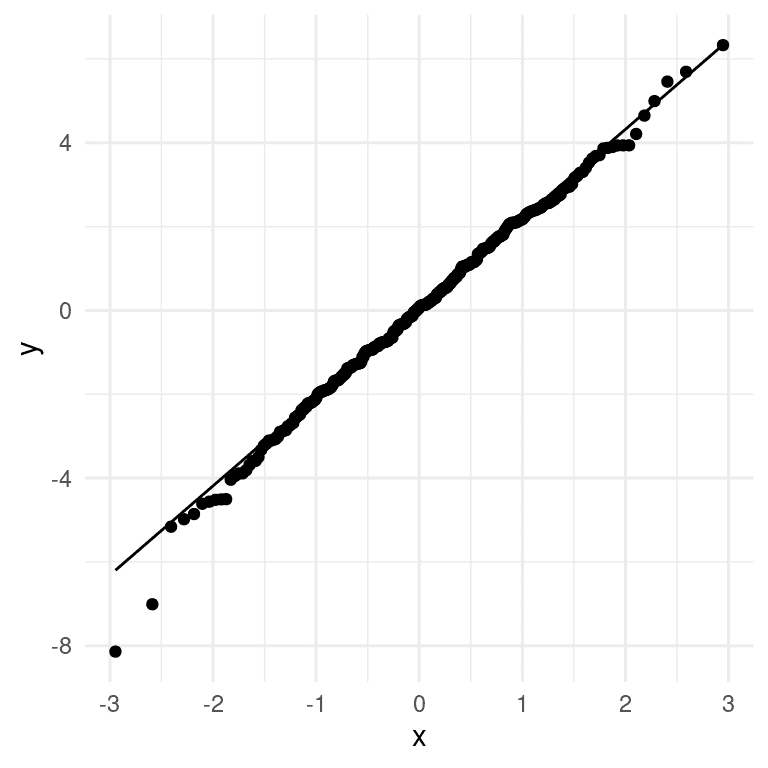

我们应用于线性模型的统计检验的另一个重要假设是模型的残差呈正态分布。人们普遍错误地认为线性模型要求数据呈正态分布,但事实并非如此;正确的统计要求只是残差误差呈正态分布。图 17.3 的右侧显示了一个 Q-Q(分位数-分位数)图,它将残差值根据正态分布中的分位数与其期望值进行了对比。如果残差呈正态分布,那么数据点应该沿着虚线分布 — 在这种情况下看起来相当不错,除了在底部明显的一些离群值。由于这个模型对正态性的违反也相对健壮,并且这些违反相当小,我们将继续使用这些结果。

图 17.3: 实际残差值与理论残差值的 Q-Q 图